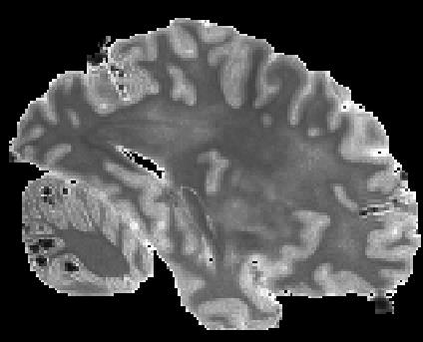

In neuroimaging, MRI tissue properties characterize underlying neurobiology, provide quantitative biomarkers for neurological disease detection and analysis, and can be used to synthesize arbitrary MRI contrasts. Estimating tissue properties from a single scan session using a protocol available on all clinical scanners promises to reduce scan time and cost, enable quantitative analysis in routine clinical scans and provide scan-independent biomarkers of disease. However, existing tissue properties estimation methods - most often $\mathbf{T_1}$ relaxation, $\mathbf{T_2^*}$ relaxation, and proton density ($\mathbf{PD}$) - require data from multiple scan sessions and cannot estimate all properties from a single clinically available MRI protocol such as the multiecho MRI scan. In addition, the widespread use of non-standard acquisition parameters across clinical imaging sites require estimation methods that can generalize across varying scanner parameters. However, existing learning methods are acquisition protocol specific and cannot estimate from heterogenous clinical data from different imaging sites. In this work we propose an unsupervised deep-learning strategy that employs MRI physics to estimate all three tissue properties from a single multiecho MRI scan session, and generalizes across varying acquisition parameters. The proposed strategy optimizes accurate synthesis of new MRI contrasts from estimated latent tissue properties, enabling unsupervised training, we also employ random acquisition parameters during training to achieve acquisition generalization. We provide the first demonstration of estimating all tissue properties from a single multiecho scan session. We demonstrate improved accuracy and generalizability for tissue property estimation and MRI synthesis.